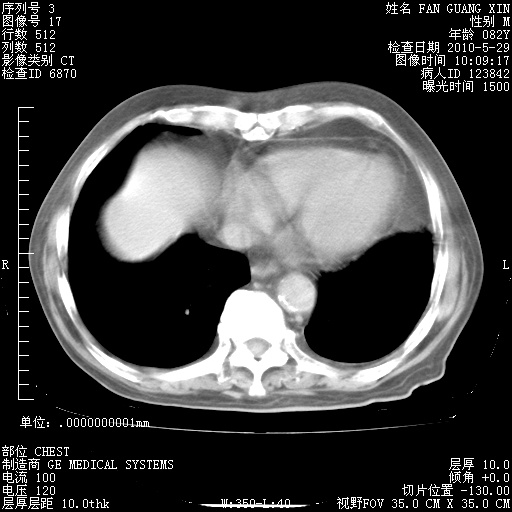

再治疗10天后的肺部CT

再治疗10天后的肺部CT 纵膈窗

肺部体征:呼吸25次/分,心率100次/分,呼吸音增粗。无干湿罗音。

血常规:15.36×10 [sup]9[/sup]/L  N0.92  L0.036  M0.045 ESR 27mm/h。

血生化:白蛋白33.30g/L  球蛋白23.67g/L  CRP 32.82mg/L 肝肾功能正常。电解质正常。

从白细胞总数和中性比例看好像合并感染。肺部纹理好像比上次多,支气管炎?其他感染?

阅读此次胸部CT,肺间质渗出性改变较入院时有吸收。目前从体温、白细胞、中性分叶明显增高,肯定存在细菌感染(发生医院感染哦,若无消化道及泌尿系统等感染的依据,肺部感染可能大)。若你院头孢哌酮舒巴坦钠耐药率较高,同意你的方案,若48小时体温仍高,可考虑使用碳青霉稀类抗菌药物,同时可予超声雾化、注意滴数时加大液体量。白蛋白33.30g/L较低哦,需加强营养等支持治疗。